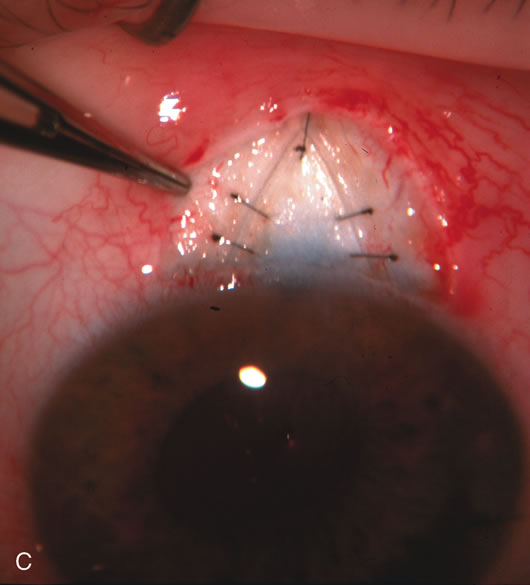

Fig. 1. The anatomic advantage of small incision cataract surgery for the glaucoma patient. A. Long-term bleb function with a large cataract incision is difficult to achieve with either ECCE-trabeculectomy or trabeculectomy followed later by ECCE. This bleb failed to form sufficiently when combined with large incision ECCE. The inflammation, bleeding, and long-term wound healing with stimulation of fibroblasts associated with this technique are more likely to cause bleb failure. In addition, the increased iris manipulation necessary to deliver the nucleus and subsequent iris repair adds to the long-term breakdown of the blood aqueous barrier. B and C. Two-site phacotrabeculectomy has the advantage of small incision cataract surgery combined with separate site trabeculectomy. The incision size is one third the size of the standard ECCE. The inflammation is less severe, and cataract wound healing is confined to the temporal area. Visual rehabilitation with phacoemulsification and foldable IOL is much faster. Phacoemulsification allows successful lens extraction even in the unfriendly environment of a smaller pupil compared with ECCE. The trabeculectomy is performed in an entirely different site, well away from the wound healing associated with temporal phacoemulsification. The likelihood of this filter functioning long-term is greater than with ECCE-trabeculectomy. D. The surgeon also has the option of single-site phacotrabeculectomy with foldable IOL. Both the lens extraction and trabeculectomy are performed through one small 3.5-mm limbal incision.

Fig. 7. Phacotrabeculectomy adjacent to a failed filter in cataractous eye. The ability to combine small-incision cataract extraction with trabeculectomy all through the same incision adjacent to the failed filter allows the surgeon to work in a familiar superior area. Avoiding incisions into the existing bleb decreases conjunctival buttonholes, hypotony, operating room time, and subconjunctival bleeding. A. Appearance of failed bleb with exposure of superior temporal quadrant gained with a corneal traction suture. B. Prepare a limbus-based conjunctival flap and a scleral flap. C. This bleb is at high risk to fail again justifying the need for MMC, 0.2 mg/cc applied on a pledget for 4 minutes. D. Insert the keratome and perform phacotrabeculectomy in the usual fashion.